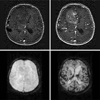

Counterexamples are used to motivate the revision of the established theory of tracer transport. Then dynamic contrast enhanced magnetic resonance imaging in particular is conceptualized in terms of a fully distributed convection-diffusion model from which a widely used convolution model is derived using, alternatively, compartmental discretizations or semigroup theory. On this basis, applications and limitations of the convolution model are identified. For instance, it is proved that perfusion and tissue exchange states cannot be identified on the basis of a single convolution equation alone. Yet under certain assumptions, particularly that flux is purely convective at the boundary of a tissue region, physiological parameters such as mean transit time, effective volume fraction, and volumetric flow rate per unit tissue volume can be deduced from the kernel.